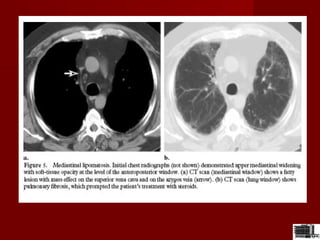

Lipom mediastinal ;masa mediastinala cu un contur

lobulat,neted si densitate negativa care inconjura fara

sa comprime artera brahiocefalica